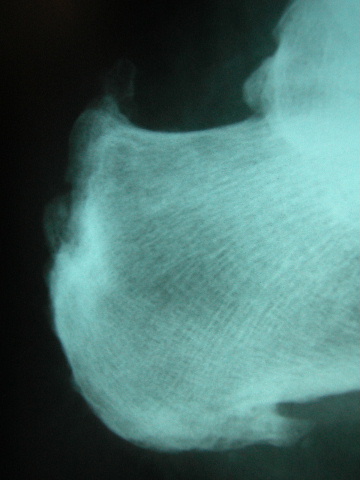

ACT espolón calcáneo y microcalcificaciones.

ACT espolones calcáneos.